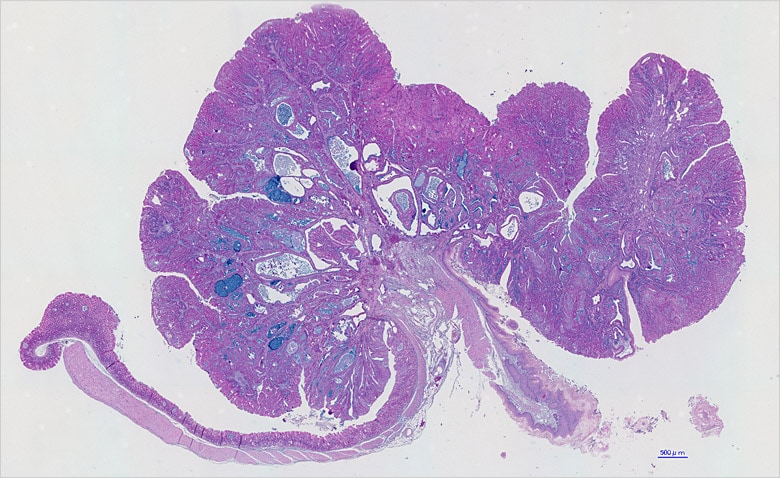

画像は『佐谷秀行:細胞工学 (2008) 27: 686-689より転載』

07. 『ヘイズリダクション』機能でクリアな画像に

佐谷研究室にてBZシリーズを頻繁に使用しているのが、共同研究員の石本崇胤氏だ。現在、胃がんの発生に関する研究を手がけている。胃がんの原因として近年、ヘリコバクター・ピロリ(ピロリ菌)の関与が明らかになっているが、in vivoにおけるそのメカニズムについては完全に解明されたわけではない。石本氏はトランスジェニックマウスを用いた研究を通じて、胃がんが発生する分子レベルでのメカニズムを突き止めようとしている。

BZシリーズについては、マウスの胃の全体像および切片の観察に用いている。

「従来、組織切片の蛍光顕微鏡での観察というと、敷居が高くて気軽に使えるものではありませんでした。第一に、観察をしようとすると、試料の入ったプレパラートを持って、別棟にある暗室に駆けつける必要があったのです。これはなかなか面倒なこと。その点、BZシリーズは研究室内に設置でき、使いたいときにいつでも使用できて重宝しています」

「何といっても画像がきれいな点が魅力です。蛍光ボケを除去できる『ヘイズリダクション』機能は重宝しています。ポイントとなる細胞が発現している様子がはっきりと分かり、説得力のある画像にできると思います」